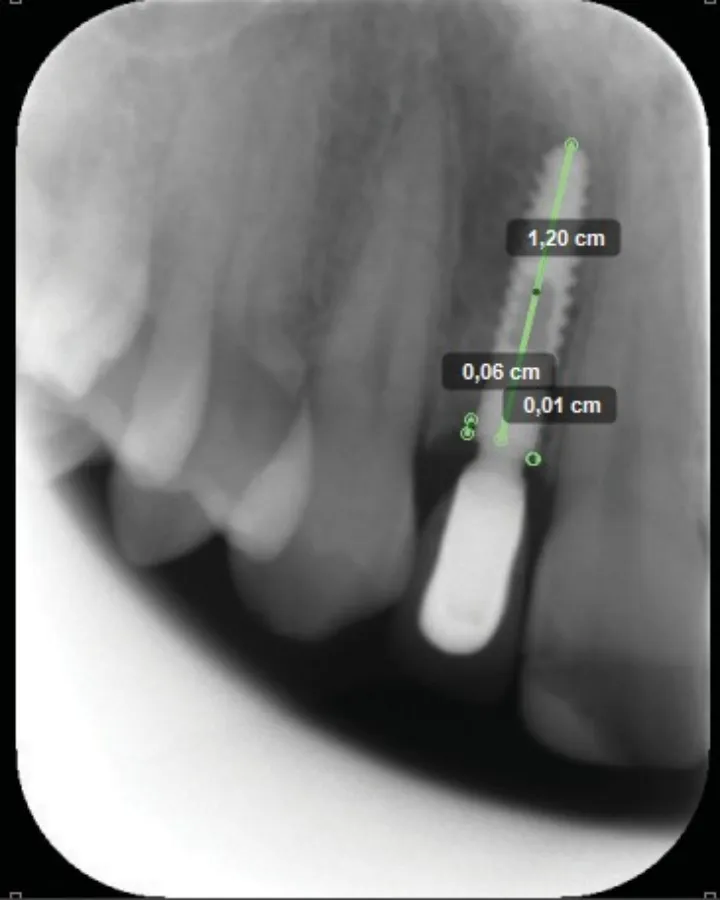

由一名独立评估人员使用 Kinovea 软件对骨组织水平进行了 X 线测量,测量结果用种植体实际长度进行校准(图 2)。研究开始时测量的骨组织水平(首次种植术时骨水平)与种植术后 1 年时测量的骨组织水平之差即为骨吸收。

平均骨组织水平经近中和远中水平值计算得出。

图2:术后 1 年近、远中骨组织水平测量值。